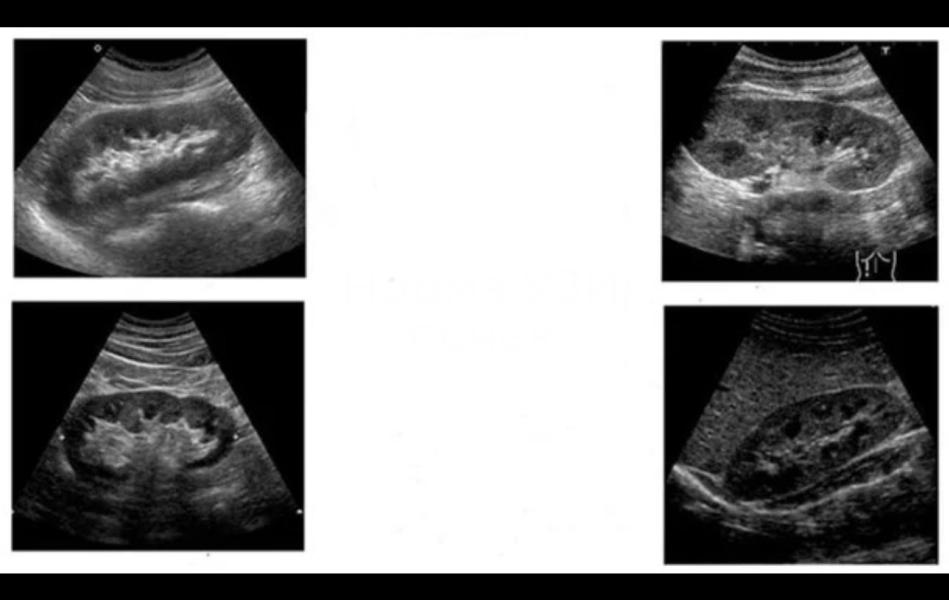

Первый снимок демонстрирует расширенную ЧЛС поражённой почки, второй показывает сильно наполненный мочевой пузырь, а третий служит примером нормальной здоровой почки для наглядного сравнения.